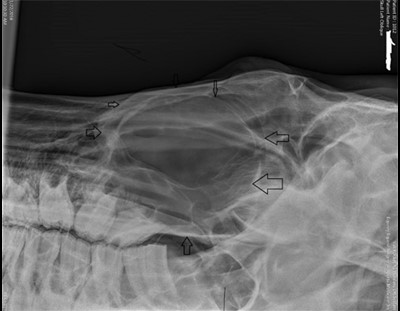

In January of 2016 at age 23 the gelding began to develop swelling under his left eye. Two referring veterinarians were consulted who felt the swelling was consistent with trauma. There are three causes of bony facial swelling in horses: 1, Infection (abscess); 2, sinus cyst and 3, cancer. Radiographs identified a smooth soft tissue mass filling the left maxillary sinus consistent with abscess or cyst.